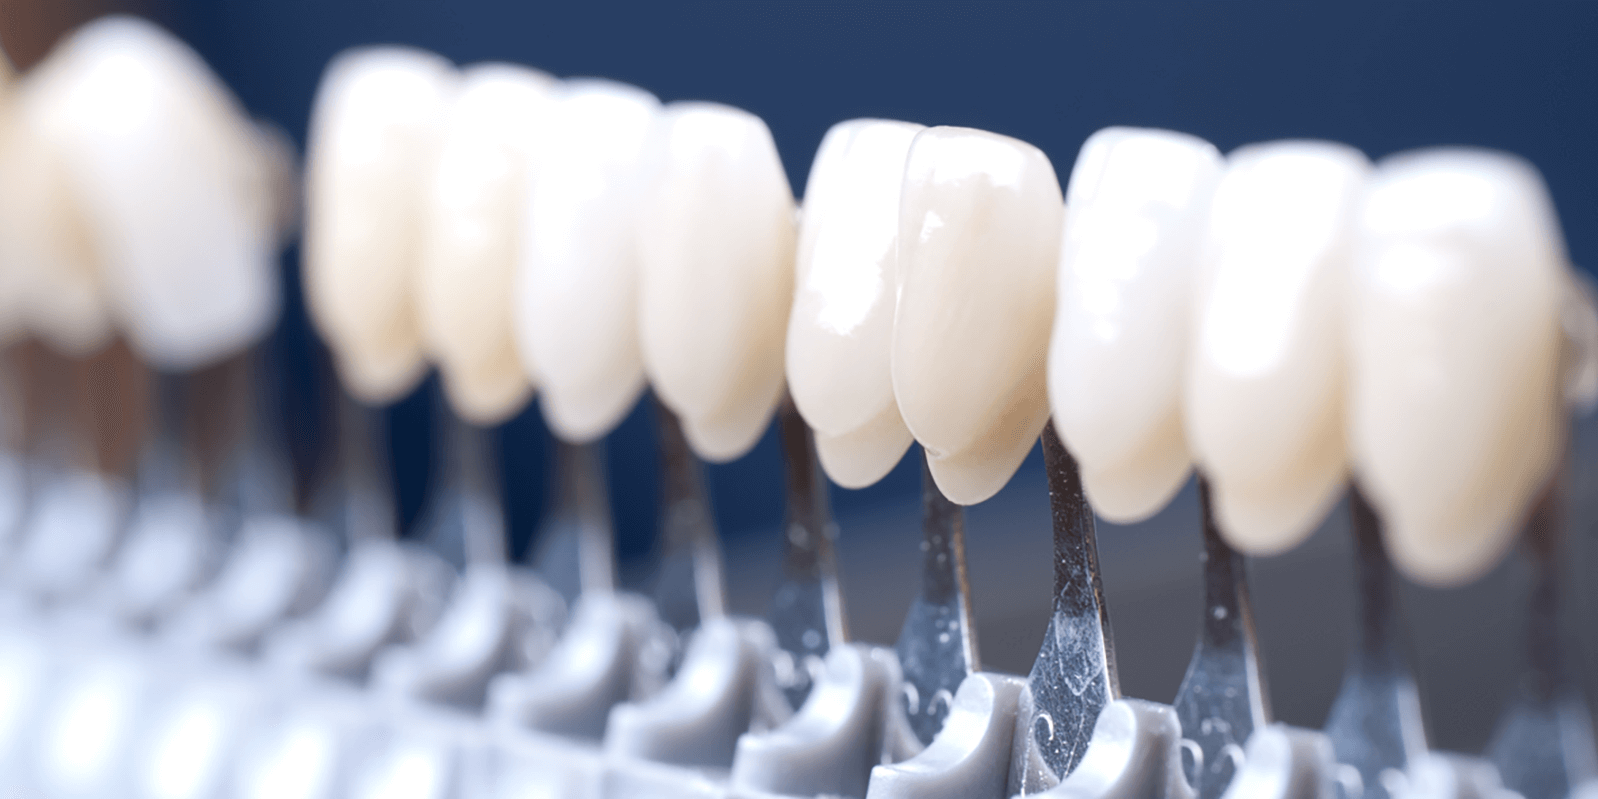

Estetik gülüş tasarımı yaptırmak isteyenler laminate veneer nedir sorusunun yanıtını merak eder. Bunlar, dişlerin ön yüzeyine uygulanan ince porselen veya kompozit kaplamalardır. Estetik diş hekimliğinde sıkça tercih edilen bu yöntem, dişlerin görünümünü iyileştirmek amacıyla kullanılır.

Laminate veneerler, dişlerdeki renk bozukluklarını, şekil bozukluklarını, aşınmaları ve aralıkları düzeltmek için tercih edilir. Bu kaplamalar, dişlerin doğal yapısını koruyarak minimum diş aşındırması ile maksimum estetik sonuçlar elde edilmesine yardımcı olur. Laminate veneerler, doğal dişlere oldukça benzer ve ışık geçirgenliği sayesinde doğal bir görünüm sunma özelliğine sahiptir. Bu nedenle gülüş estetiğini iyileştirmek isteyen bireyler için oldukça iyi bir seçenektir.

- Laminate veneerler, dişlerin doğal görünümüne çok yakın bir estetik sağlayabilir. Renk ve şekil açısından kişiye özel olarak tasarlanır; böylece doğal dişlerinizle mükemmel uyum gösterebilir.